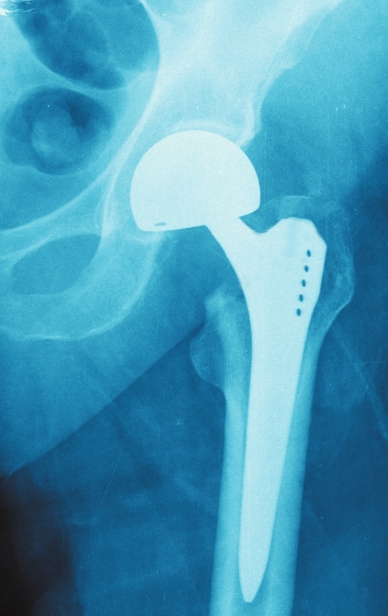

Total hip replacement surgery is extremely common, with more than 300,000 total hip replacements being performed in the United States annually. A total hip replacement procedure can be performed using a variety of surgical approaches, but the posterior approach, direct lateral approach, and direct anterior approach are by far the most common across the globe. Traditionally, most hip replacements have been done utilizing the posterior approach and direct lateral approach, where the surgeon accesses the hip through the side or buttocks. More recently, the anterior approach, where the surgeon enters from the front of the hip, has increased in popularity. The different approaches and whether one approach is better or produces a more optimal outcome have come under some debate. Does it matter if the surgeon enters either from the front of the body (anterior) versus the side/back (posterior) in a total hip replacement? Does one approach lead to a better outcome or faster recovery time? According to recent studies, the answer is no. The surgical approach to total hip replacement (THR) has no impact on outcomes six months following surgery. There is no difference if the surgical approach is to go from the front of the body (anterior) or the side/back (posterior).

This study conducted at Saint Francis Hospital & Medical Center in Hartford, Conn., involved 274 patients, who underwent THR between June 2012 and August 2014. Patients had THR with a surgeon either exclusively performing direct anterior approach or exclusively performing a posterior approach. The two groups were compared on the following: pre-/post-operative pain, function in daily living, function in sports and recreation, and hip-related quality of life. This study was presented at the annual meeting of the American Academy of Orthopedic Surgeons in March of 2016. Numerous other studies have been conducted and ultimately have come to the same conclusion.